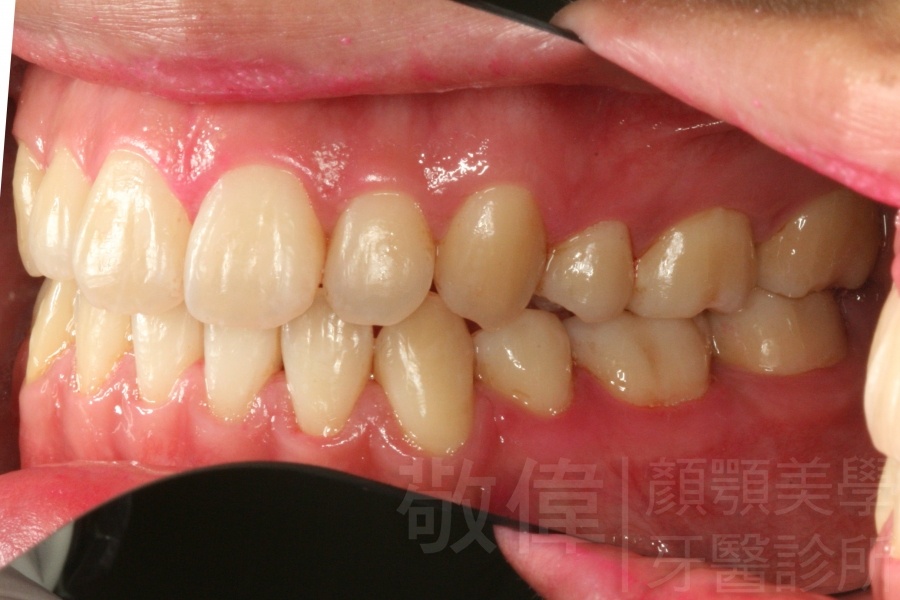

齒顏矯正/戽斗、亂牙、爛牙,變身 免植牙的健牙美女

<個案說明>

變臉矯正,原來戽斗妹跟大歪臉變成自信正妹

經由本院3D數影X光影像儀分析、與3D齒顎顏矯正技術,再配合口腔顎面正顎專科醫師施以正顎手術治療,雙方共同合作,使患者臉部外觀有很好的改善,大歪變小歪,產生了天南地北的大改變,她的人生也整個變得不一樣。

因為矯正與正顎手術的配合,使「戽斗妹」變成了「陽光正妹」,完全的改變了她的人生,在面對各種場合、與人交際都散發出自信微笑。所以,奉勸家長,如果小朋友有臉顎畸型的問題,應該考慮配合做這種簡單、安全、有效的正顎手術。